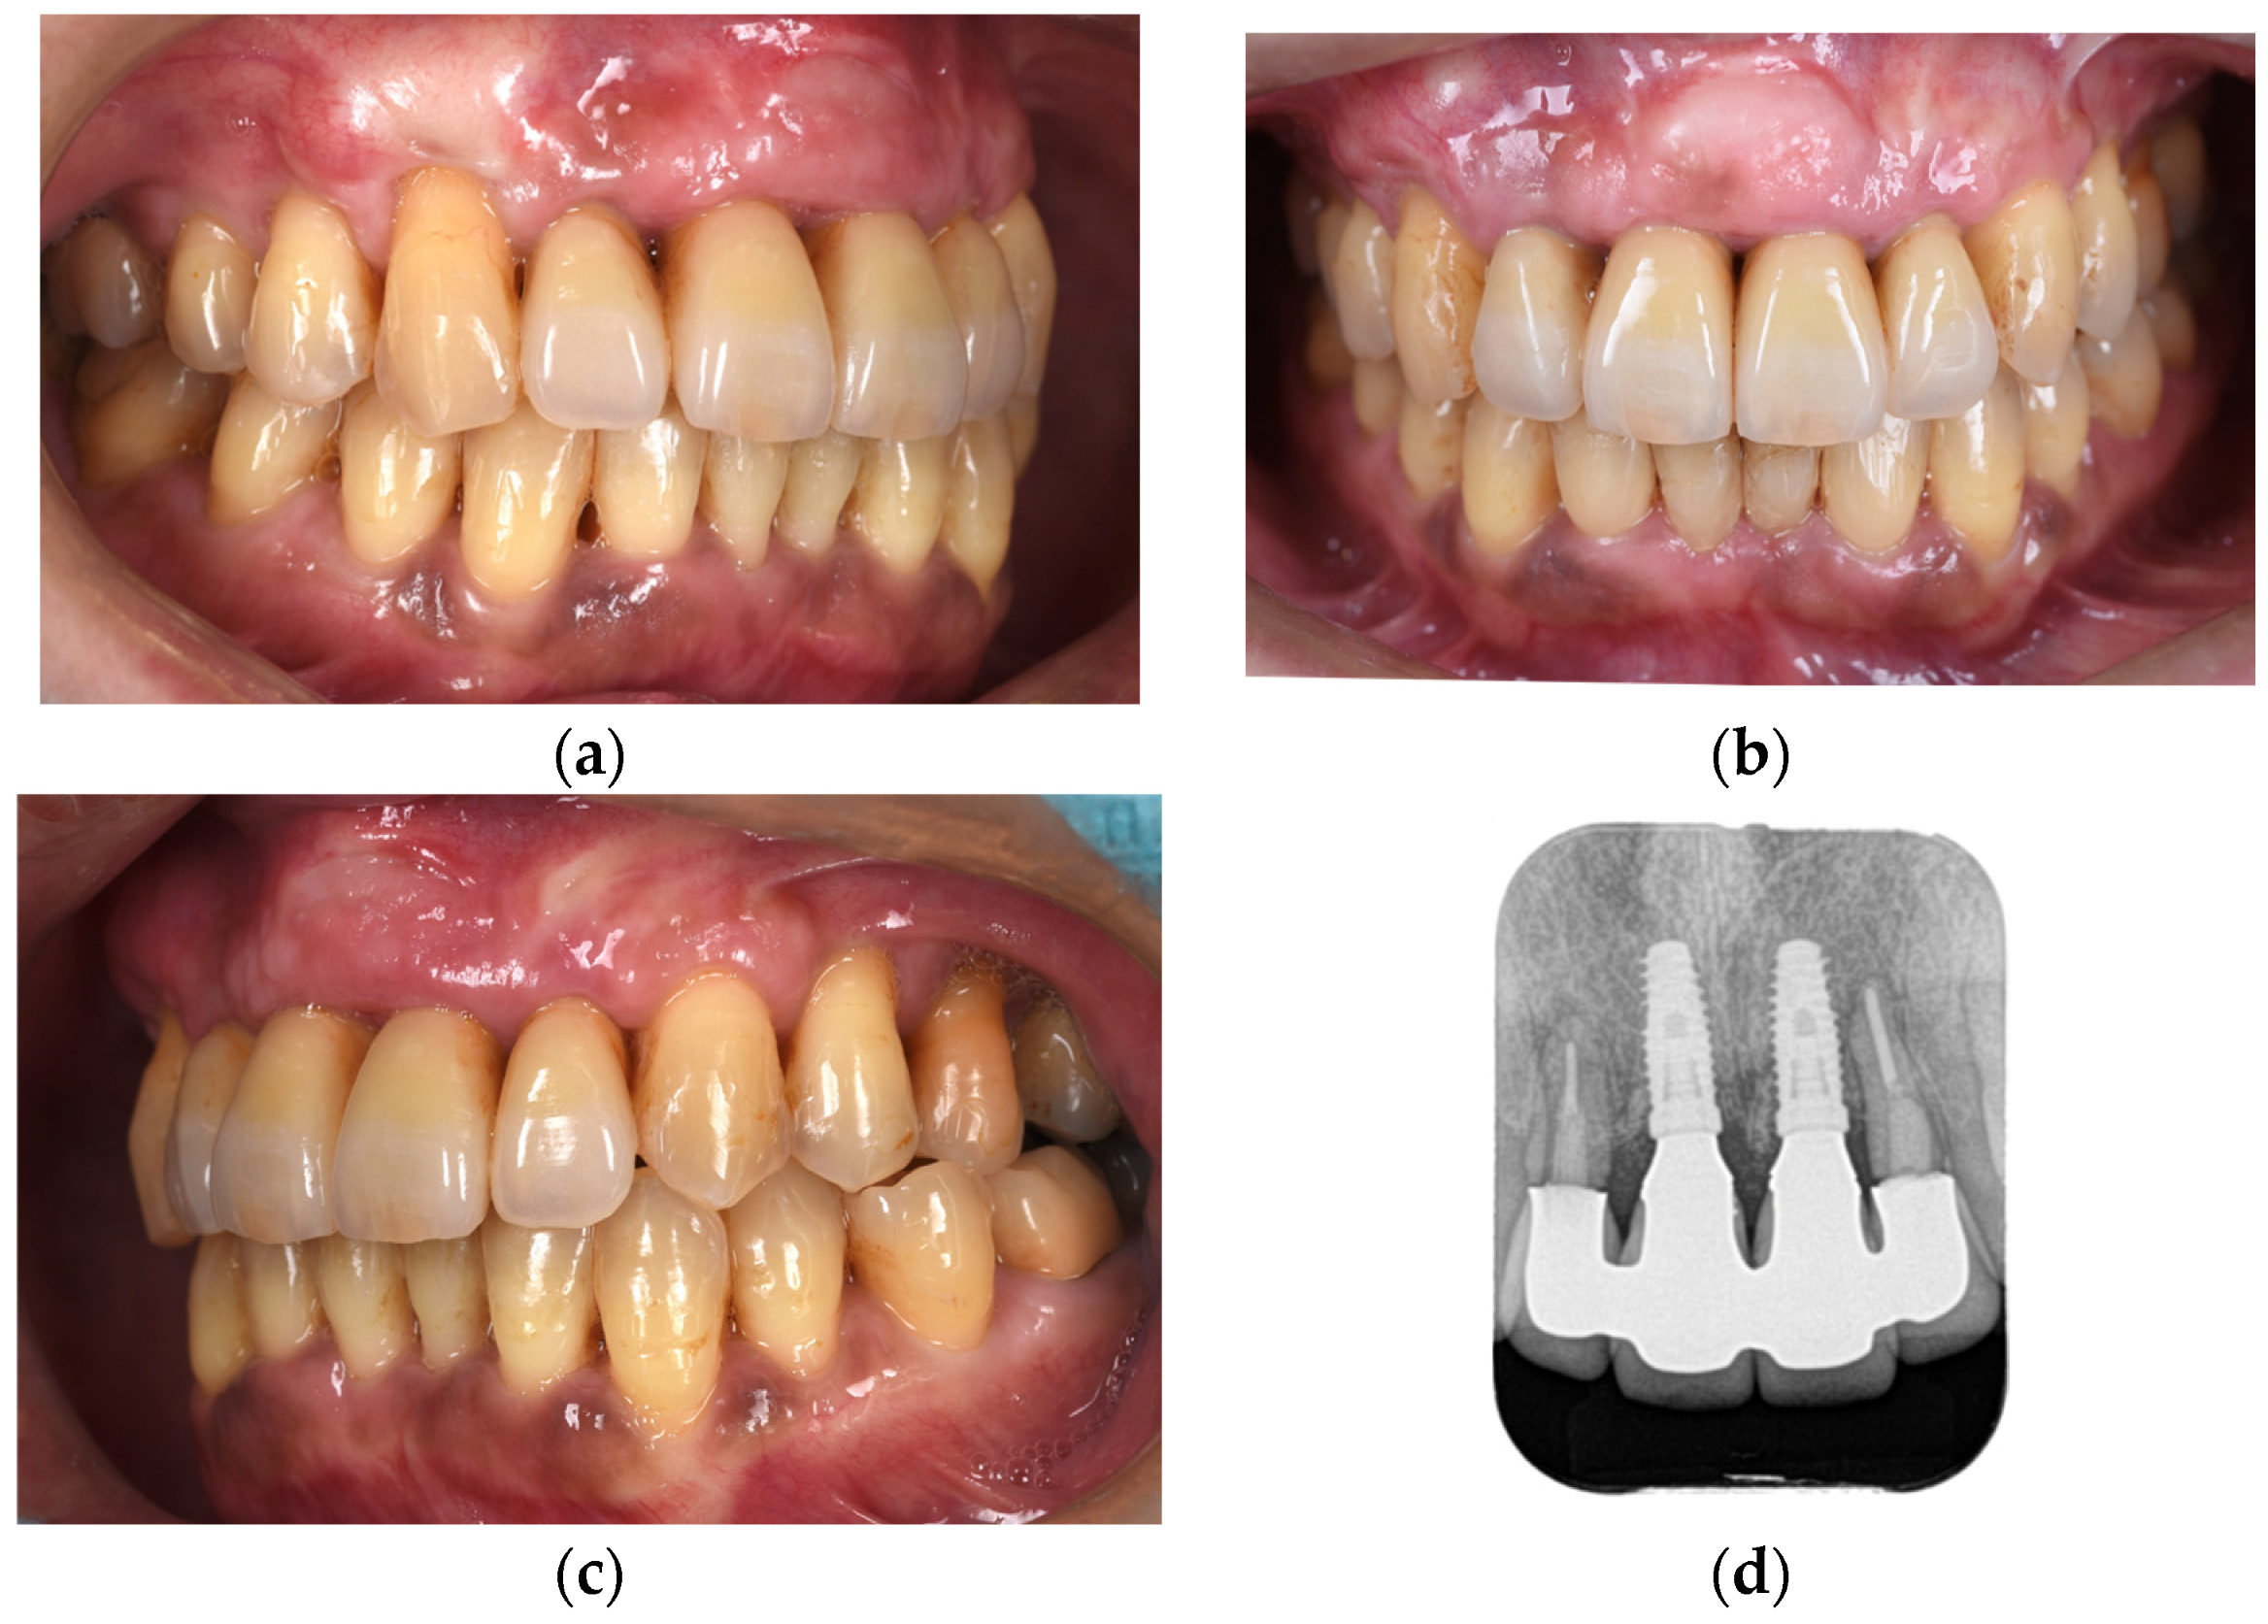

Figure 10. Right-lateral (a), frontal (b), and left-lateral (c) views and dental radiograph (d) obtained immediately after the cementation of the final prosthesis.

The second-stage implant exposure procedure was conducted in March 2017. Subsequently, a connective tissue graft was applied to enhance the soft tissue volume and improve aesthetic outcomes (Figure 9a). Provisional restorations were placed (Figure 9b), and orthodontic treatment was initiated (Figure 9c). The orthodontic treatment was completed in February 2018. Although the implant on the left side was in close proximity to the adjacent tooth, no clinical issues were observed around the implant or in the remaining teeth immediately after placement or during the provisional restoration period. Therefore, porcelain-fused-to-zirconia restorations were installed in the month (Panavia; Kuraray Noritake Dental Inc., Niigata, Japan) (Figure 10). Due to the low bone support of the maxillary bilateral lateral incisors and potential complications, screw retention was preferable to allow prosthetic device replacement. However, the structural complexity of the connection with the natural teeth makes screw retention difficult; therefore, the superstructure was cemented. Although provisional cementation would have been ideal for potential reprosthetics, luting cement was used to prevent intrusion of natural teeth. The patient’s oral aesthetics showed notable enhancement since the initial consultation, as depicted in Figure 11.

Following the completion of prosthetic treatment, maintenance appointments were scheduled every 3 months. After a 5-year maintenance period, the gingival tissue showed no significant alterations in shape or color, and the adjacent teeth maintained proper functionality (Figure 12). The periodontal status of the patients changed minimally immediately after the placement of the final prosthesis and at the 5-year follow-up (Figure 13).